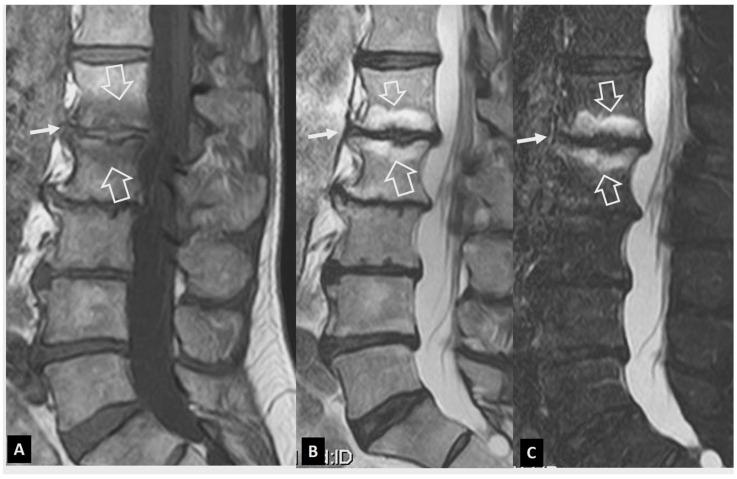

A series of conditions can mimic musculoskeletal infections on imaging, complicating their diagnosis and affecting the treatment. Depending on the anatomical location, different conditions can manifest with clinical and imaging findings that mimic infections. Herein we present a wide spectrum of the musculoskeletal disorders of the axial skeleton, long bones, peripheral joints, and soft tissue that may manifest as infectious processes, and we focus on the potential mimics of osteomyelitis, septic arthritis, and infectious spondylodiscitis that are common in clinical practice. We present the typical imaging characteristics of each musculoskeletal infection, followed by mimicking conditions.

一系列病症在影像学上可模拟肌肉骨骼感染,使诊断复杂化并影响治疗。根据解剖位置的不同,不同病症可表现出类似感染的临床和影像学表现。在此,我们展示了轴向骨骼、长骨、外周关节和软组织的广泛肌肉骨骼疾病,这些疾病可能表现为感染过程,并且我们重点关注临床实践中常见的骨髓炎、化脓性关节炎和感染性脊椎间盘炎的潜在模仿病症。我们介绍了每种肌肉骨骼感染的典型影像学特征,随后是模仿病症。